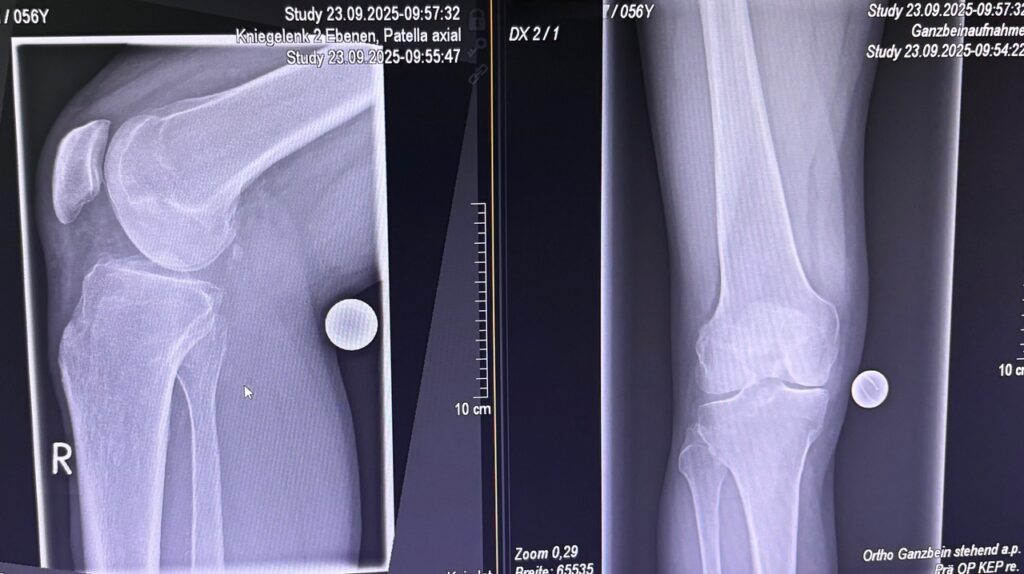

Η ημιολική αρθροπλαστική γόνατος (partial / unicompartmental knee replacement) είναι επέμβαση όπου αντικαθίσταται μόνο το φθαρμένο διαμέρισμα του γόνατος και όχι ολόκληρη η άρθρωση.

Πότε ενδείκνυται

- Οστεοαρθρίτιδα ενός μόνο διαμερίσματος:

- έσω (συχνότερα)

- έξω

- επιγονατιδομηριαίο

- Σχετικά περιορισμένη παραμόρφωση

Ημιολική vs Ολική αρθροπλαστική

| Χαρακτηριστικό | Ημιολική | Ολική |

| Έκταση επέμβασης | Μικρή | Μεγάλη |

| Αίσθηση γόνατος | Πολύ φυσική | Καλή |

| Ανάρρωση | Ταχύτερη | Πιο αργή |

| Κατάλληλη για όλους | Όχι | Ναι |

| Διάρκεια εμφυτεύματος | Πολύ καλή (σε σωστές ενδείξεις) | Άριστη |

- σωστή διάγνωση

Η τελική επιλογή της χειρουργικής τεχνικής γίνεται μετά από αναλυτική κλινική αξιολόγηση και προσεκτικό προεγχειρητικό σχεδιασμό, με στόχο το βέλτιστο και ασφαλέστερο αποτέλεσμα για τον ασθενή. Απαραίτητη προϋπόθεση για την επίτευξη εξαιρετικών αποτελεσμάτων αποτελεί η εξειδίκευση του χειρουργού στη συγκεκριμένη τεχνική, καθώς και η εκτεταμένη εμπειρία με μεγάλο αριθμό επεμβάσεων. Ο έμπειρος ορθοπαιδικός Νικόλαος Καλύβας εφαρμόζει την Ημιολική αρθροπλαστική γόνατος (Μονοδιαμερισματική) επί σειρά ετών στη Γερμανία, έχοντας χειρουργήσει μεγάλο αριθμό ασθενών. Τα τελευταία χρόνια, από τη θέση του Αναπληρωτή Διευθυντή σε ένα από τα μεγαλύτερα κέντρα αρθροπλαστικής της Γερμανίας, είχε ενεργό ρόλο στην εκπαίδευση ειδικευομένων ορθοπαιδικών στη συγκεκριμένη τεχνική.